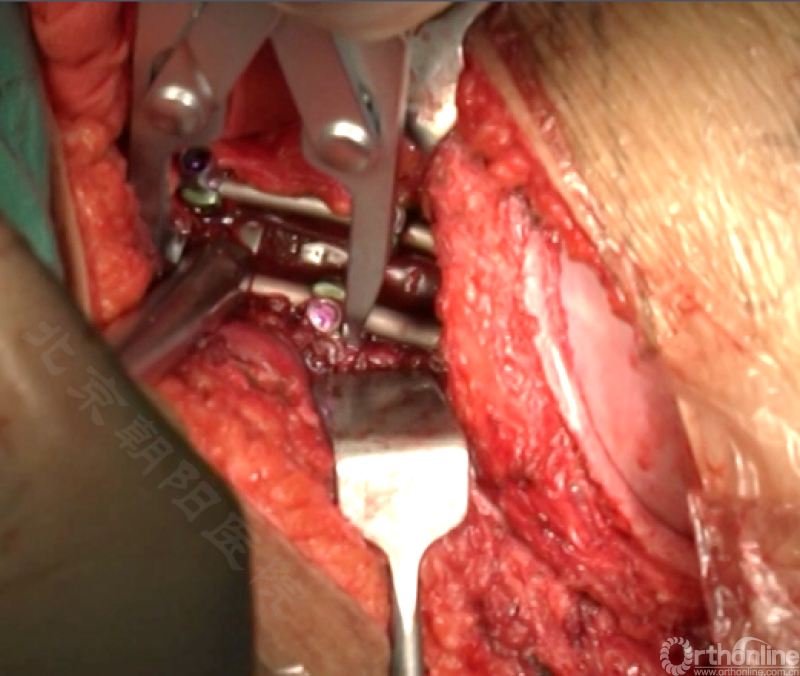

内固定选择的是5.5mm双棒系统,先置入顶椎的螺钉垫板。

置入顶椎的椎体螺钉,螺钉可置入椎体中部到后方1/3之间的范围内。

使用双棒系统时,先置入背侧的螺钉,螺钉指向椎体中线,后置入腹侧的螺钉,螺钉轻度指向后侧。形成对椎体的三角形抓持力。

胸腔侧、腹腔侧螺钉全部置入后,骨移植物植人的越靠近后纵韧带或者纤维环的后缘越好。

将预先折弯的金属棒先置入背侧。

椎间融合器经前方置入凹侧,确保腰椎前凸的恢复和冠状面畸形的矫正,将剩下的骨移植物置入椎间隙内。

置入腹侧金属棒。

使用双棒系统时先安装背侧的棒,可进行90°的去旋转,也可以直接通过前方螺钉矫正冠状面和矢状面的畸形,然后固定后方的棒,可进一步通过加压矫正冠状面畸形。

矫正后神经检测未见异常术中唤醒患者下肢活动良好,术中透视矫正效果满意、内固定位置良好。根据手术具体情况放置合适尺寸的横连接加强内固定。